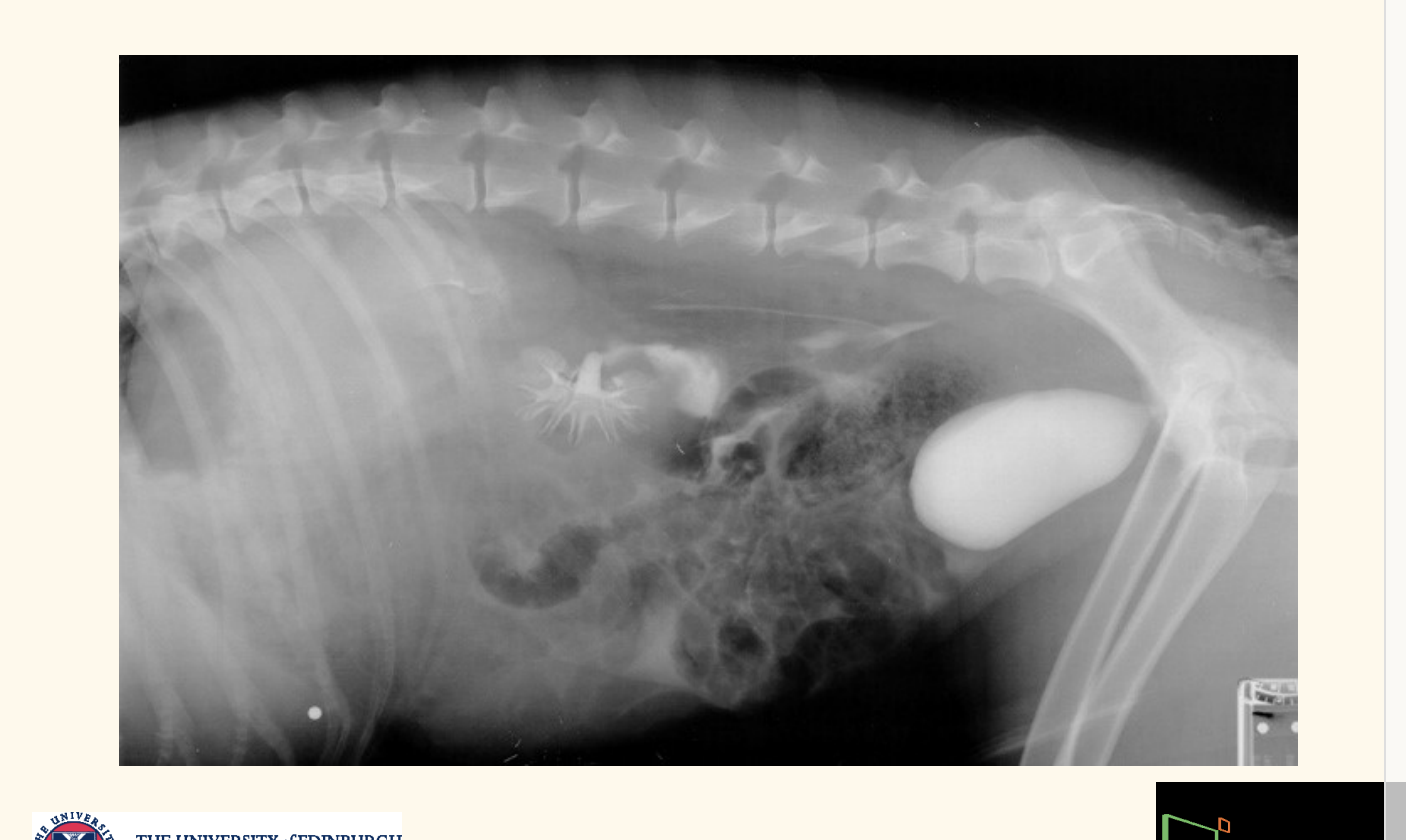

what deos this contrast radiography shoe

leakage of contrast into abdomen

urethrea lost…